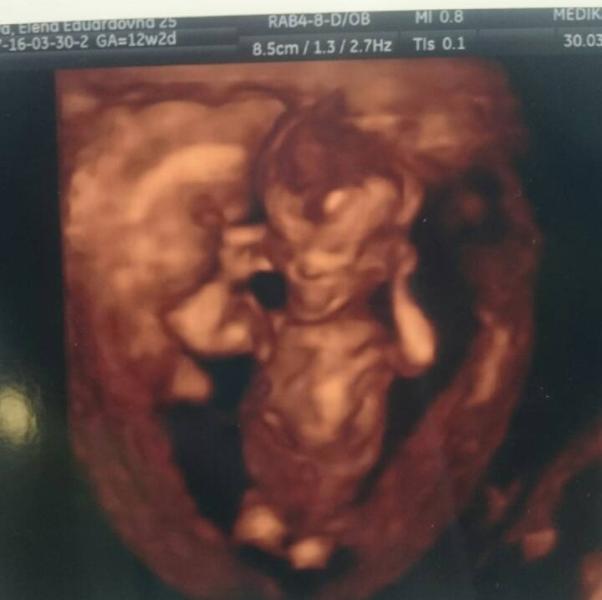

Сегодня ходили на первое УЗИ. Ведусь в Медике на Пулковской, чтобы сто раз туда не мотаться, решила сразу в один день и УЗИ сделать, и сдать все 30 видов крови. Вот только проблема в том, что меня тошнит по утрам, тошнит, когда я хочу есть, тошнит в такси и я падаю в обморок, когда берут кровь 😁